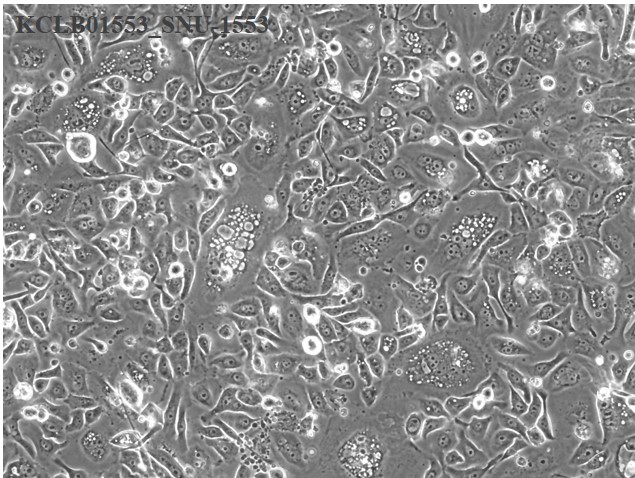

| Cellular morphology |

epithelial

| Growth Pattern |

monolayer